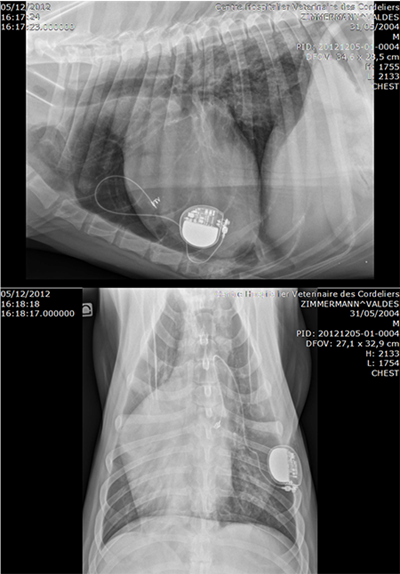

Leads

- Medtronic Unipolar electrodes for single chamber pacing

- Capsure EPI 4965 coated with steroïds

- Suturelessunipolar myocardial screw-in pacing lead

- Pulse generator : VVIR Medtronic ADAPTA ADSR 01

- 15 mm portal for lead implatation

- Lead and electrode positionning

- Controle pacing